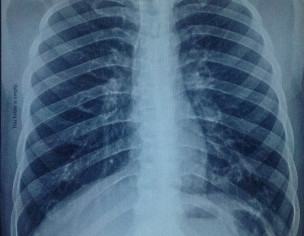

kindly examine the two chest x-rays from two different labs. my bro was hired job in UAE but in medical test he is declared unfit because of some kind of x-ray findings. These x-rays images are taken from two different labs from the 1st one where he was medically examined. Expert reviews required from radiologist and pulmonologist.

is B/l hilar prominence with old heald of the countries not accept these findings even if you dont have history of old or new infection/TB.

There is difference in exposure in both films. Any symptoms like fever, weight loss etc. Age of patient, smoking history?Dr Khawaja Yassir Rahman

2nd xray has some whitish shades in ur language like lymphednopathy

just because of this they reject

otherwise if pt is asymptomTic xray is normL

if he has cough short of breath he should go for Ace levels n ct scan